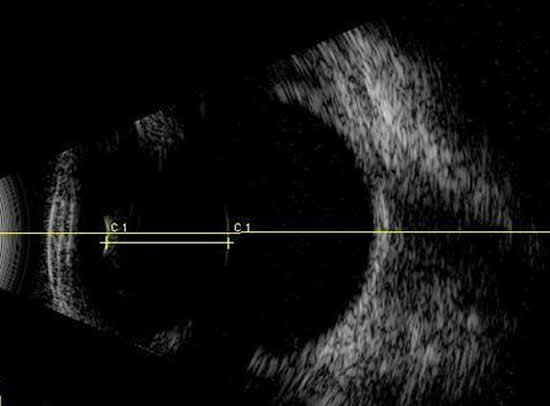

En medicina veterinaria, nuestros pacientes pocas veces presentan síntomas a no ser que la patología esté desencadenando estadíos fínales. Es en este momento cuando nos encontramos opacidades: edema corneal, endotelitis, turbiedad de humor acuoso por uveítis, cataratas, etc que impiden visualizar los componentes del ojo. La oftalmoscopia pasa a un segundo plano, recurriendo al ultrasonido.

En la actualidad se considera la modalidad de imagen como elección en el diagnóstico y control de las enfermedades oculares.